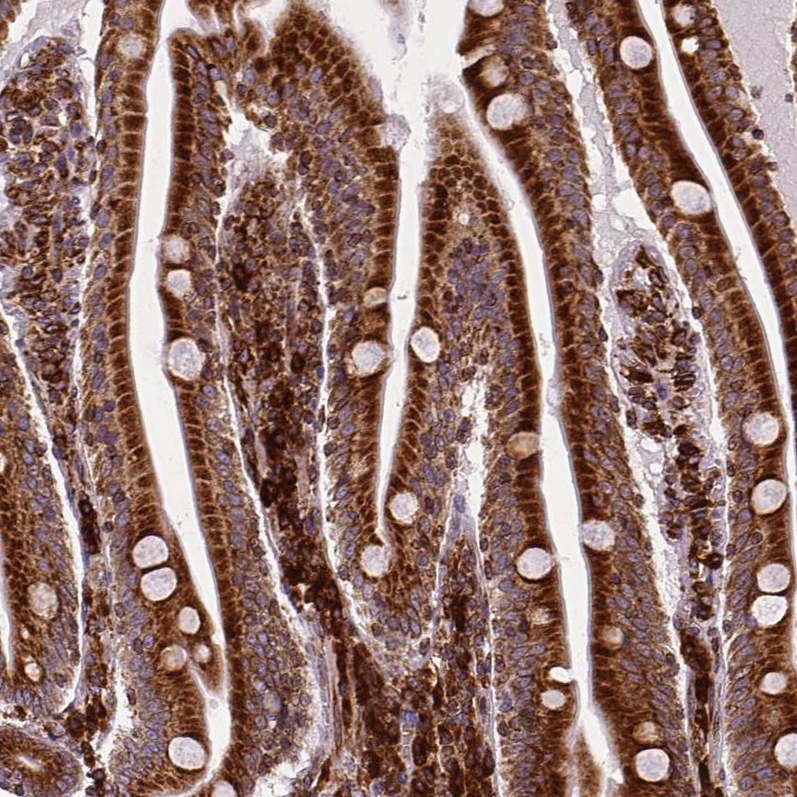

Immunohistochemical staining of human breast cancer shows strong cytoplasmic positivity in tumor cells.